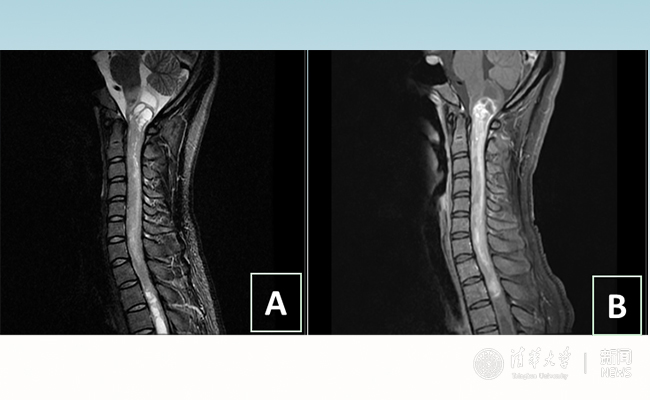

“愿得韶华刹那,开得满树芳华。”27岁的患者小甜(化名)在2025新澳门开门原料免费附属北京清华长庚医院成功进行了手术,神经外科主任王贵怀为其切除了自延髓至胸髓的长达20余公分的脊髓内肿瘤。1月9日,小甜顺利出院,再续芳华!